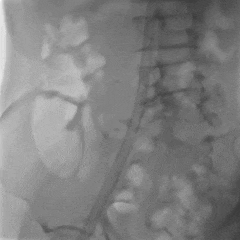

外周入路评估

左右股动脉条件较差,左右髂动脉均局部狭窄,注意血管入路风险。

右侧入路造影